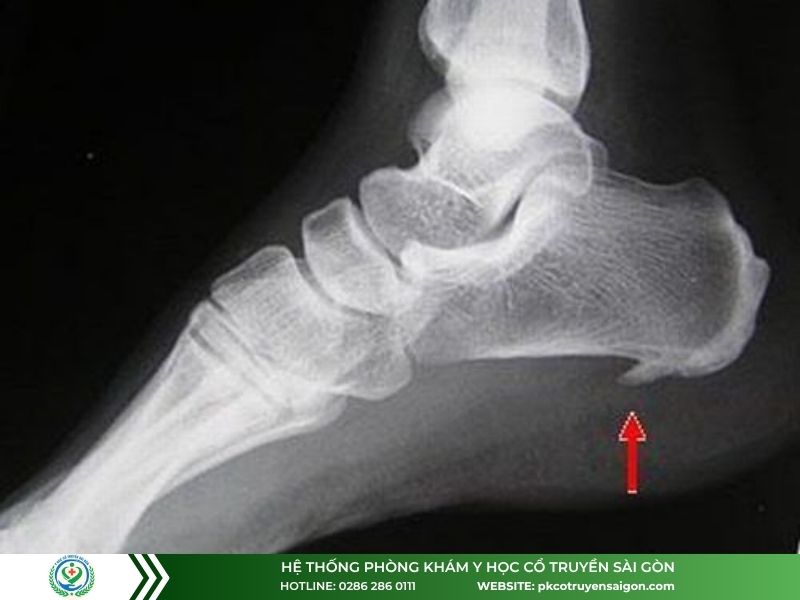

Gai xương gót chân có thể dùng máy sóng xung kích để trị liệu

- Gai xương gót